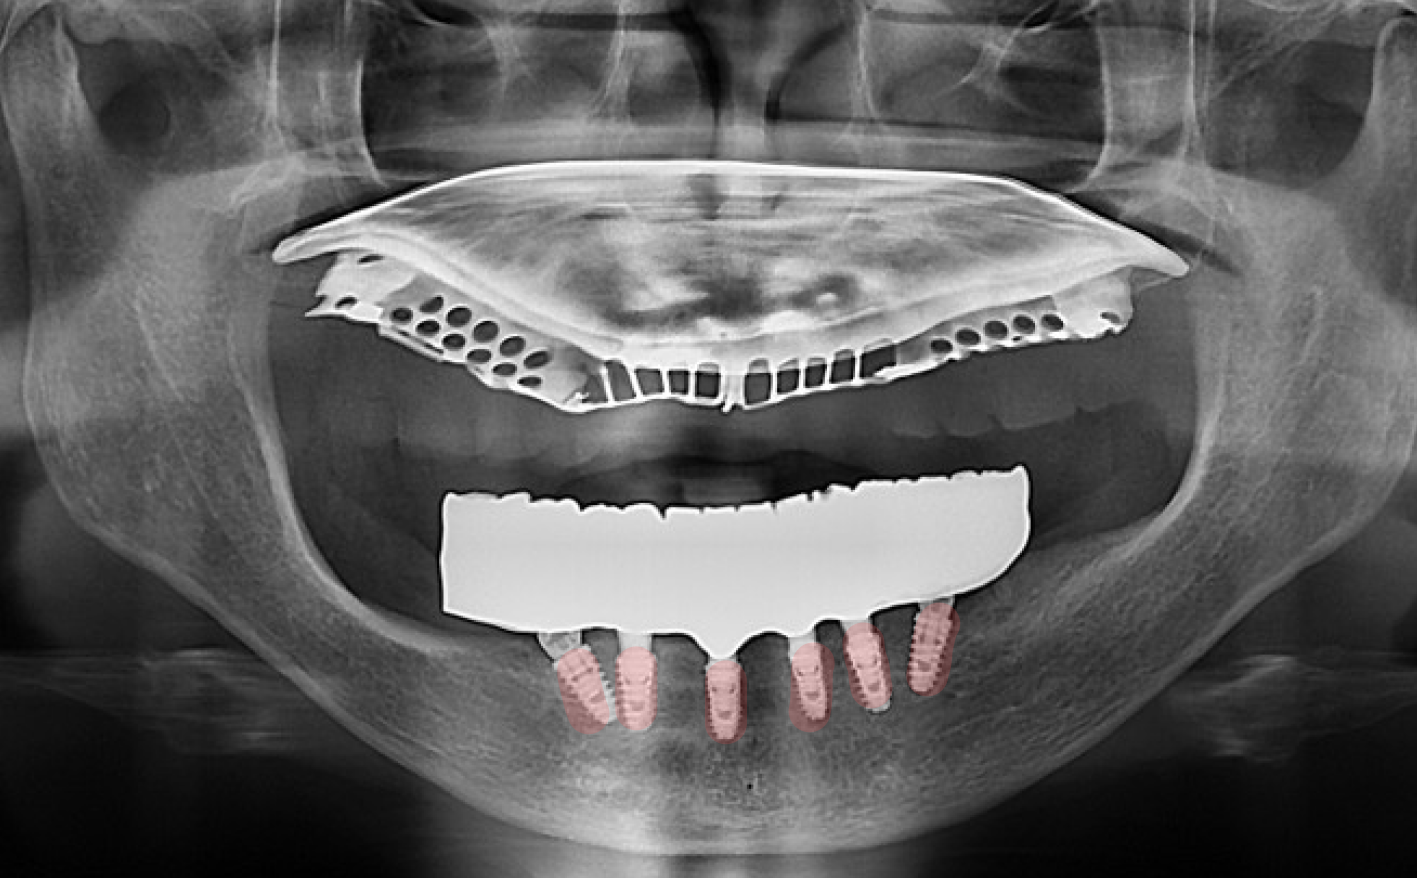

이번 사례에서는 '올온식스' 공법을 적용했습니다.

• 핵심 원리: 가장 튼튼한 뼈 위치에 6개의 임플란트 기둥을 전략적으로 식립합니다.

• 브릿지 결합: 심어진 6개의 기둥 위에 하나의 일체형 전체 보철물을 연결하여 전체 치열을 회복합니다.

• 장점: 식립 개수가 적어 비용 부담은 줄이면서도, 저작력(씹는 힘)은 자연치아의 80% 이상까지 끌어올릴 수 있습니다.

이번 환자분도 어금니 쪽 뼈가 부족하고 신경선이 가까워 일반적인 수직 식립이 어려운 상태였습니다.

저희 하루임플치과에서는 전방부의 단단한 기저골을 활용해 임플란트를 일부러 기울여 심는 ‘각도 조절 설계’를 적용했습니다.

이는 집도의의 풍부한 임상 경험이 뒷받침되어야 하는 고난도 기법으로

별도의 대규모 뼈이식 없이도 당일 임플란트 식립을 가능하게 합니다.